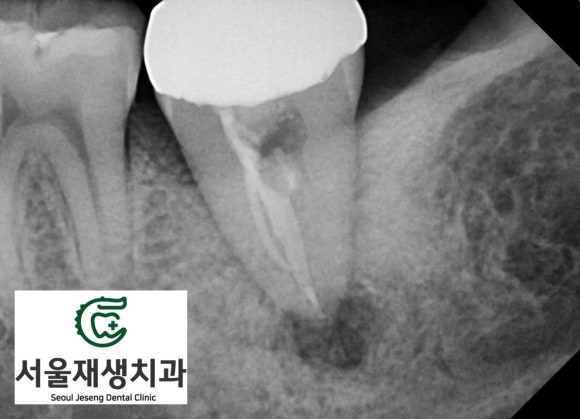

치아 머리에 있던

크라운과 각종 때운 재료들을

모두 제거합니다.

이후, 뿌리에 남아있는

이전 신경치료 재료들,

잔존 감염조직들을 모두

깨끗하게 청소합니다.

마지막으로

소독약제를 도포합니다.

위 엑스레이 사진에서

뿌리 끝까지

약제가 들어간 것을

확인할 수 있습니다.